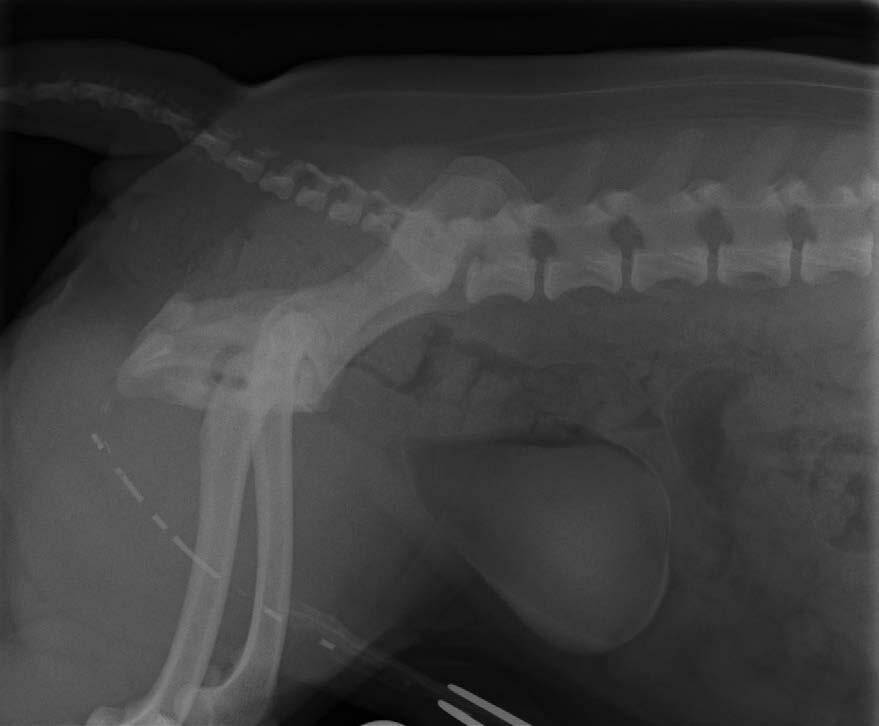

Plain lateral and ventrodorsal survey films should be taken, followed by bladder catheterisation and drainage (Figure 2).

The bladder disease that most commonly affects dogs is urolithiasis (Barrett, 2011). Radiopaque calculi are easily visualised using radiography (Figure 8) or as radiolucent filling defects when surrounded by positive contrast (Thrall, 1998), usually in the centre of the contrast puddle.

Radiopaque and radiolucent calculi appear as multiple or individual focal hyperechoic formations with distal acoustic shadowing on ultrasound (Nyland et al., 2002). They move within the bladder lumen due to gravity and may be associated with bladder wall thickening (Osborne et al., 2009). Radiographs are more accurate to predict stone size, as ultrasound can overestimate the size by up to 68 percent (Byl et al., 2010).